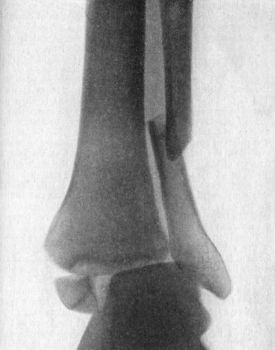

94.Radiogram of Pott's Fracture, with Lateral Displacement of Foot187

95.Ambulant Splint of Plaster of Paris189

96.Dupuytren's Splint applied to Correct Eversion of Foot190

97.Syme's Horse-shoe Splint applied to Correct Backward Displacement of Foot191